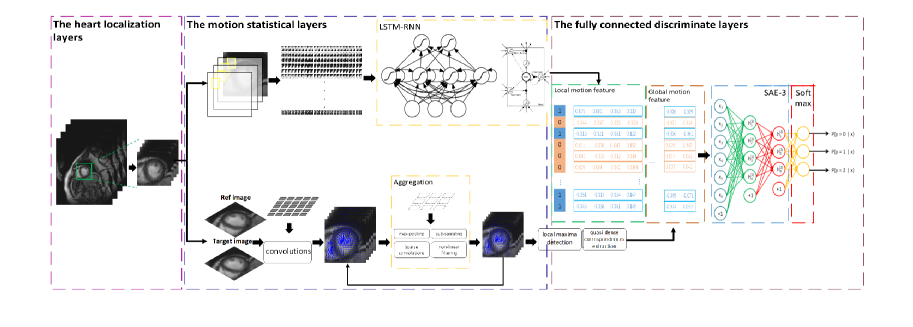

Accurate detection of the myocardial infarction (MI) area is crucial for early diagnosis planning and follow-up management. In this study, we propose an end-to-end deep-learning algorithm framework (OF-RNN ) to accurately detect the MI area at the pixel level. Our OF-RNN consists of three different function layers: the heart localization layers, which can accurately and automatically crop the region-of-interest (ROI) sequences, including the left ventricle, using the whole cardiac magnetic resonance image sequences; the motion statistical layers, which are used to build a time-series architecture to capture two types of motion features (at the pixel-level) by integrating the local motion features generated by long short-term memory-recurrent neural networks and the global motion features generated by deep optical flows from the whole ROI sequence, which can effectively characterize myocardial physiologic function; and the fully connected discriminate layers, which use stacked auto-encoders to further learn these features, and they use a softmax classifier to build the correspondences from the motion features to the tissue identities (infarction or not) for each pixel. Through the seamless connection of each layer, our OF-RNN can obtain the area, position, and shape of the MI for each patient. Our proposed framework yielded an overall classification accuracy of 94.35% at the pixel level, from 114 clinical subjects. These results indicate the potential of our proposed method in aiding standardized MI assessments.

As shown in Fig. 1, there are three function layers inside the OF-RNN. The heart localization layers can automatically detect the ROI, including the LV, and the motion statistical layers can generate motion features that accurately characterize myocardial physiologic and physical function, followed by the fully connected discriminate layers that use stacked auto-encoders and softmax classifiers to detect the MI area from motion features.

Heart localization layers. One FAST R-CNN [9] is used here for the automatic detection of a region of interest (ROI) around the LV, to reduce the computational complexity and improve the accuracy. In this study, the first process of the heart localization layers is to generate category-independent region proposals. Afterward, a typical convolutional neural network model is used to produce a convolution feature map by input images. Then, for each object proposed, an ROI pooling layer extracts a fixed-length feature vector from the feature map. The ROI pooling layer uses max pooling to convert the features inside any valid region of interest into a small feature map with a fixed spatial extent of , where and are layer hyper-parameters that are independent of any particular ROI. Finally, each feature vector is fed into a sequence of fully connected layers that branch into two sibling output layers, thereby generating a 6464 bounding-box for cropping the ROI image sequences, including the LV from CMR sequences.

Motion statistical layers. The motion statistical feature layers are used to extract time-series image motion features through ROI image sequences to understand the periodic nature of ghd heart motion. The local motion features are generated by LSTM-RNN, and the global motion features are generated by deep optical flow.

Thus, in the first step, we attempt to compute the local motion features that are extracted from the ROI image sequence. For each ROI sequence, the input image of size 6464, represents a pixel coordinate of the image . A window of size 1111 is constructed for the overlapping neighborhoods, which has an intensity value that is representative of the feature of each on image . This approach results in the image sequence features being unrolled as vector for each pixel as input. Then, four layers of RNN [10] with LSTM cells layers are used to learn the input.

Fully connected discriminate layers. The fully connected discriminate layers are used to detect the MI area accurately from the local motion features and the global motion features. First, for each , we use image patches, say 33, by extracting the feature beginning from a point in the first frame and tracing in the following frame. We can thereby obtain while containing a 33 vector for displacement and a 33 vector for the orientation of for each frame. Second, we conduct a simple concatenation between the local image feature from the LSTM-RNN and the motion trajectories feature via optical flow, to establish a whole feature vector . Finally, an auto-encoder with three stacking layers is used for learning the , followed by a softmax layer, which is used to determine whether belongs to the MI area or not.